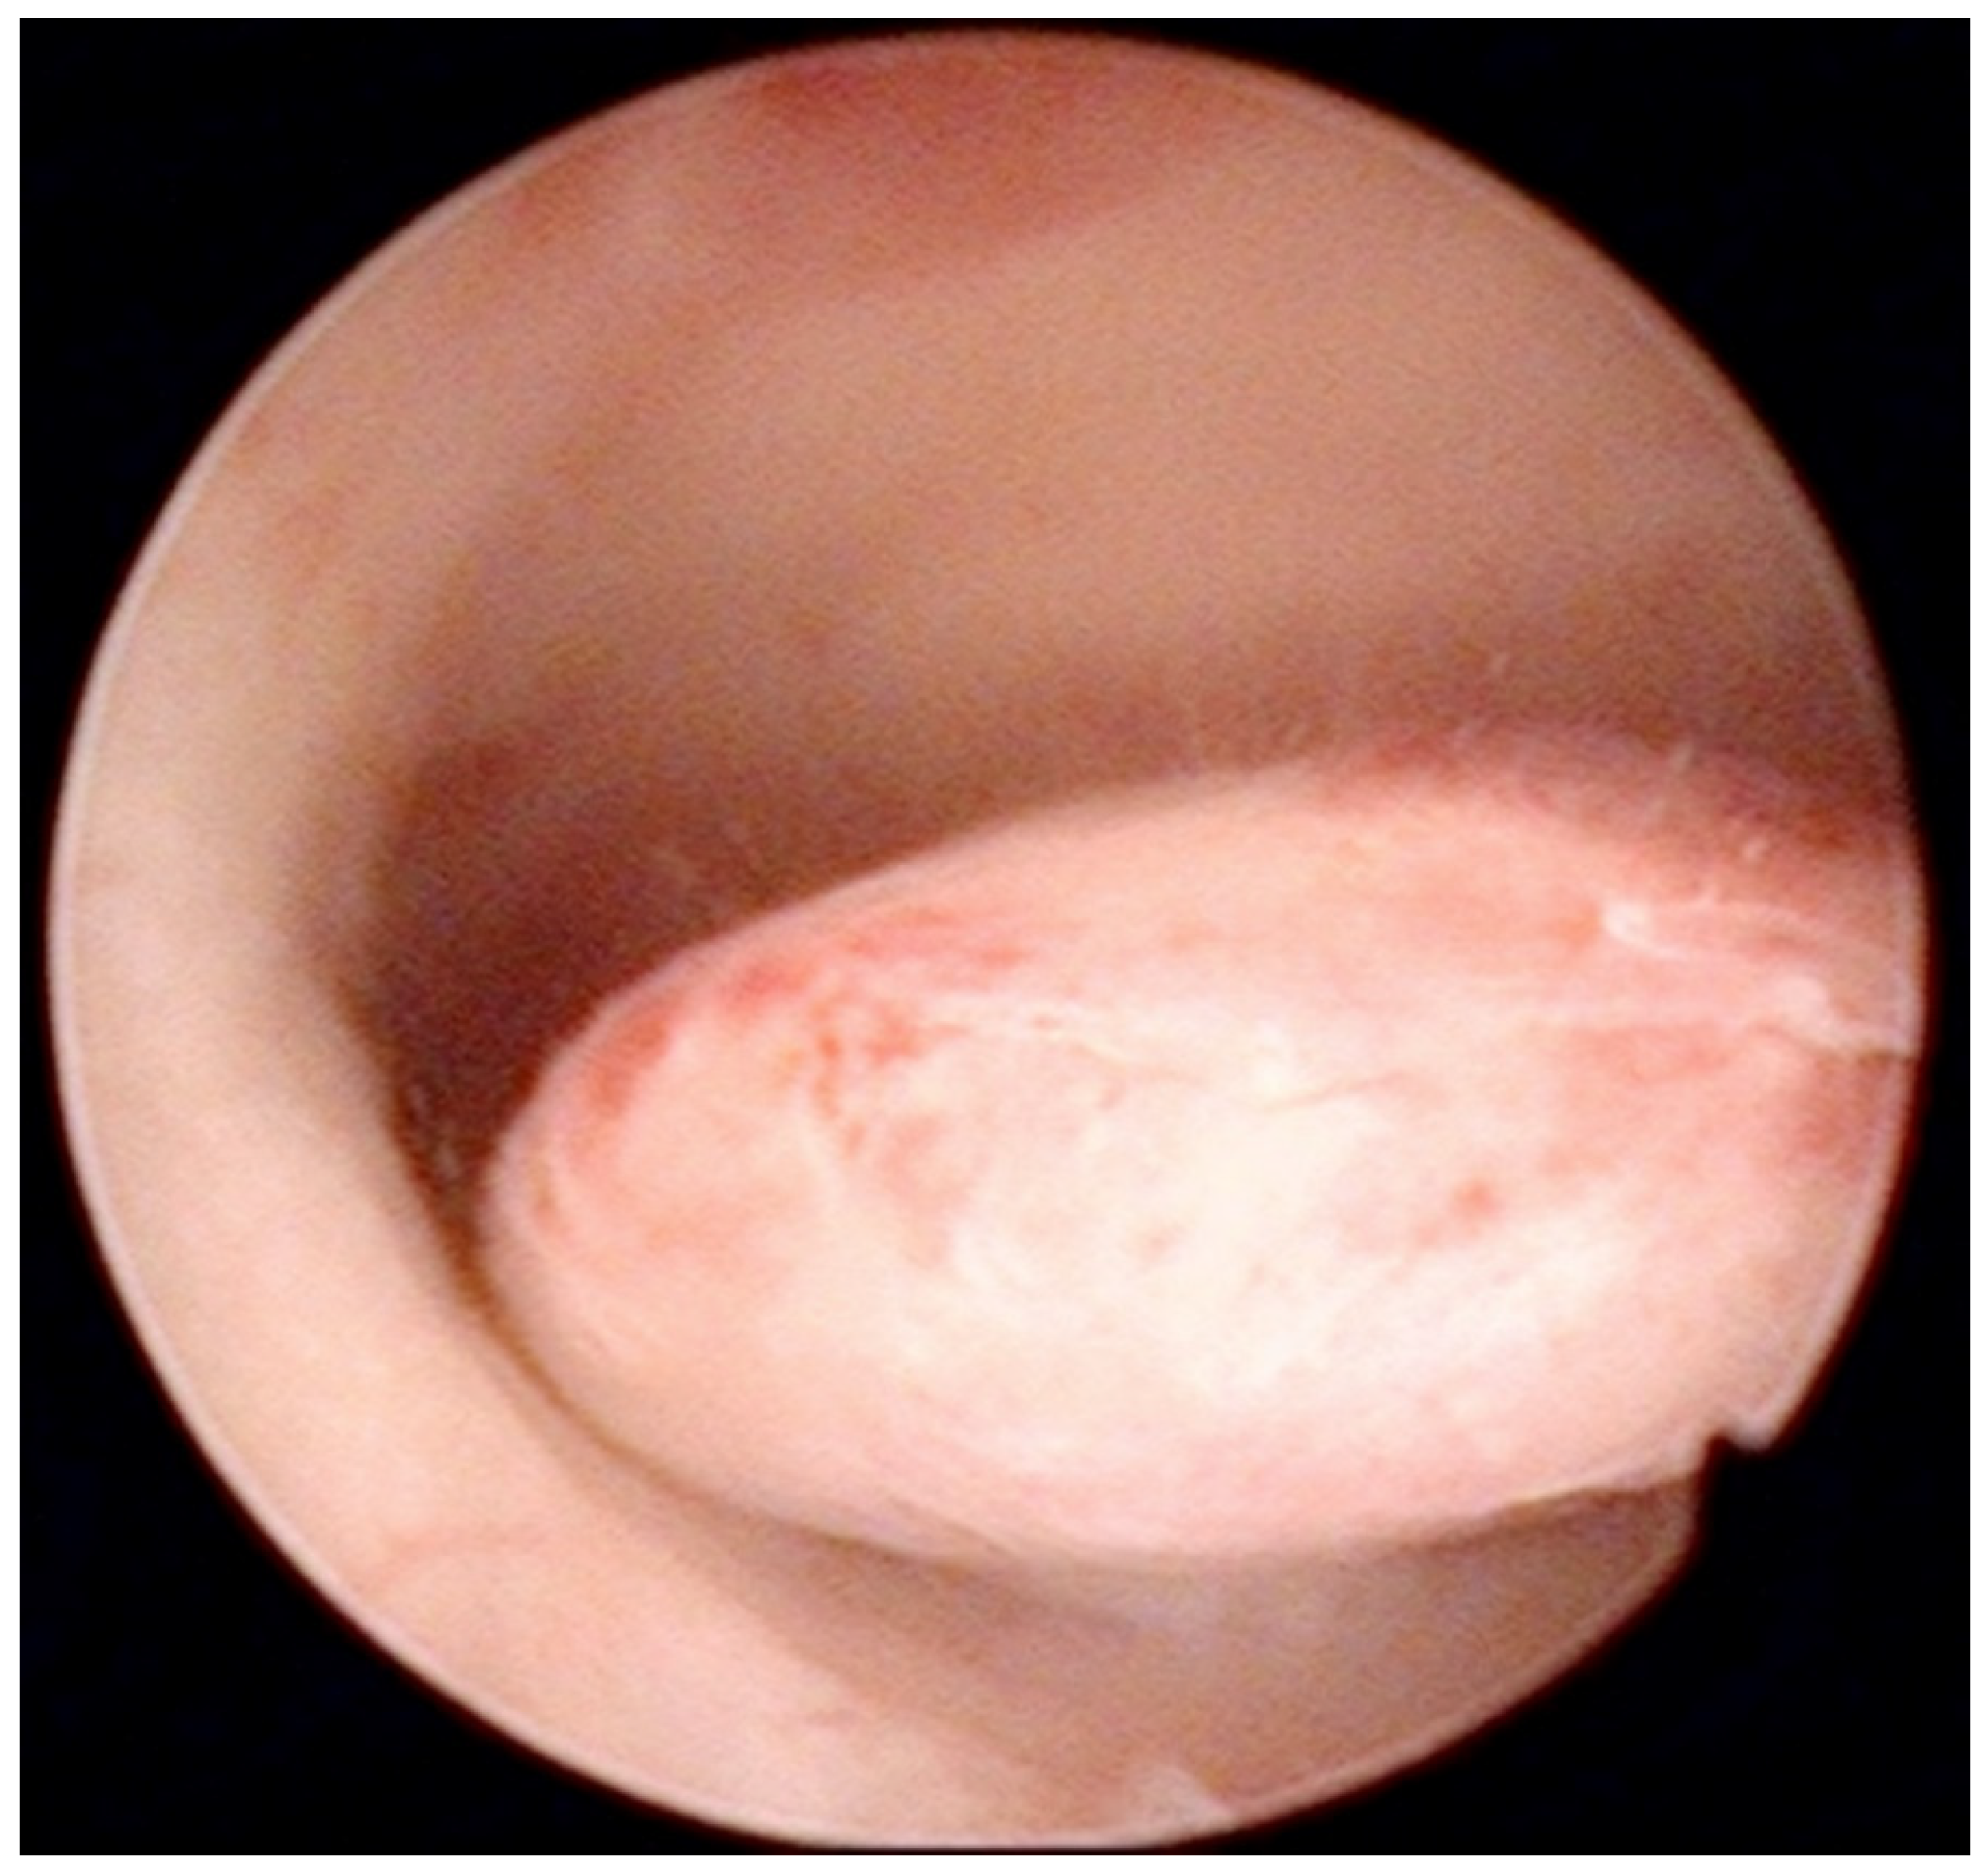

Figure 2.

Pedunculate low-risk endometrial polyp in the posterior uterine wall during diagnostic hysteroscopy (intraoperative picture by F.B. and S.F.).